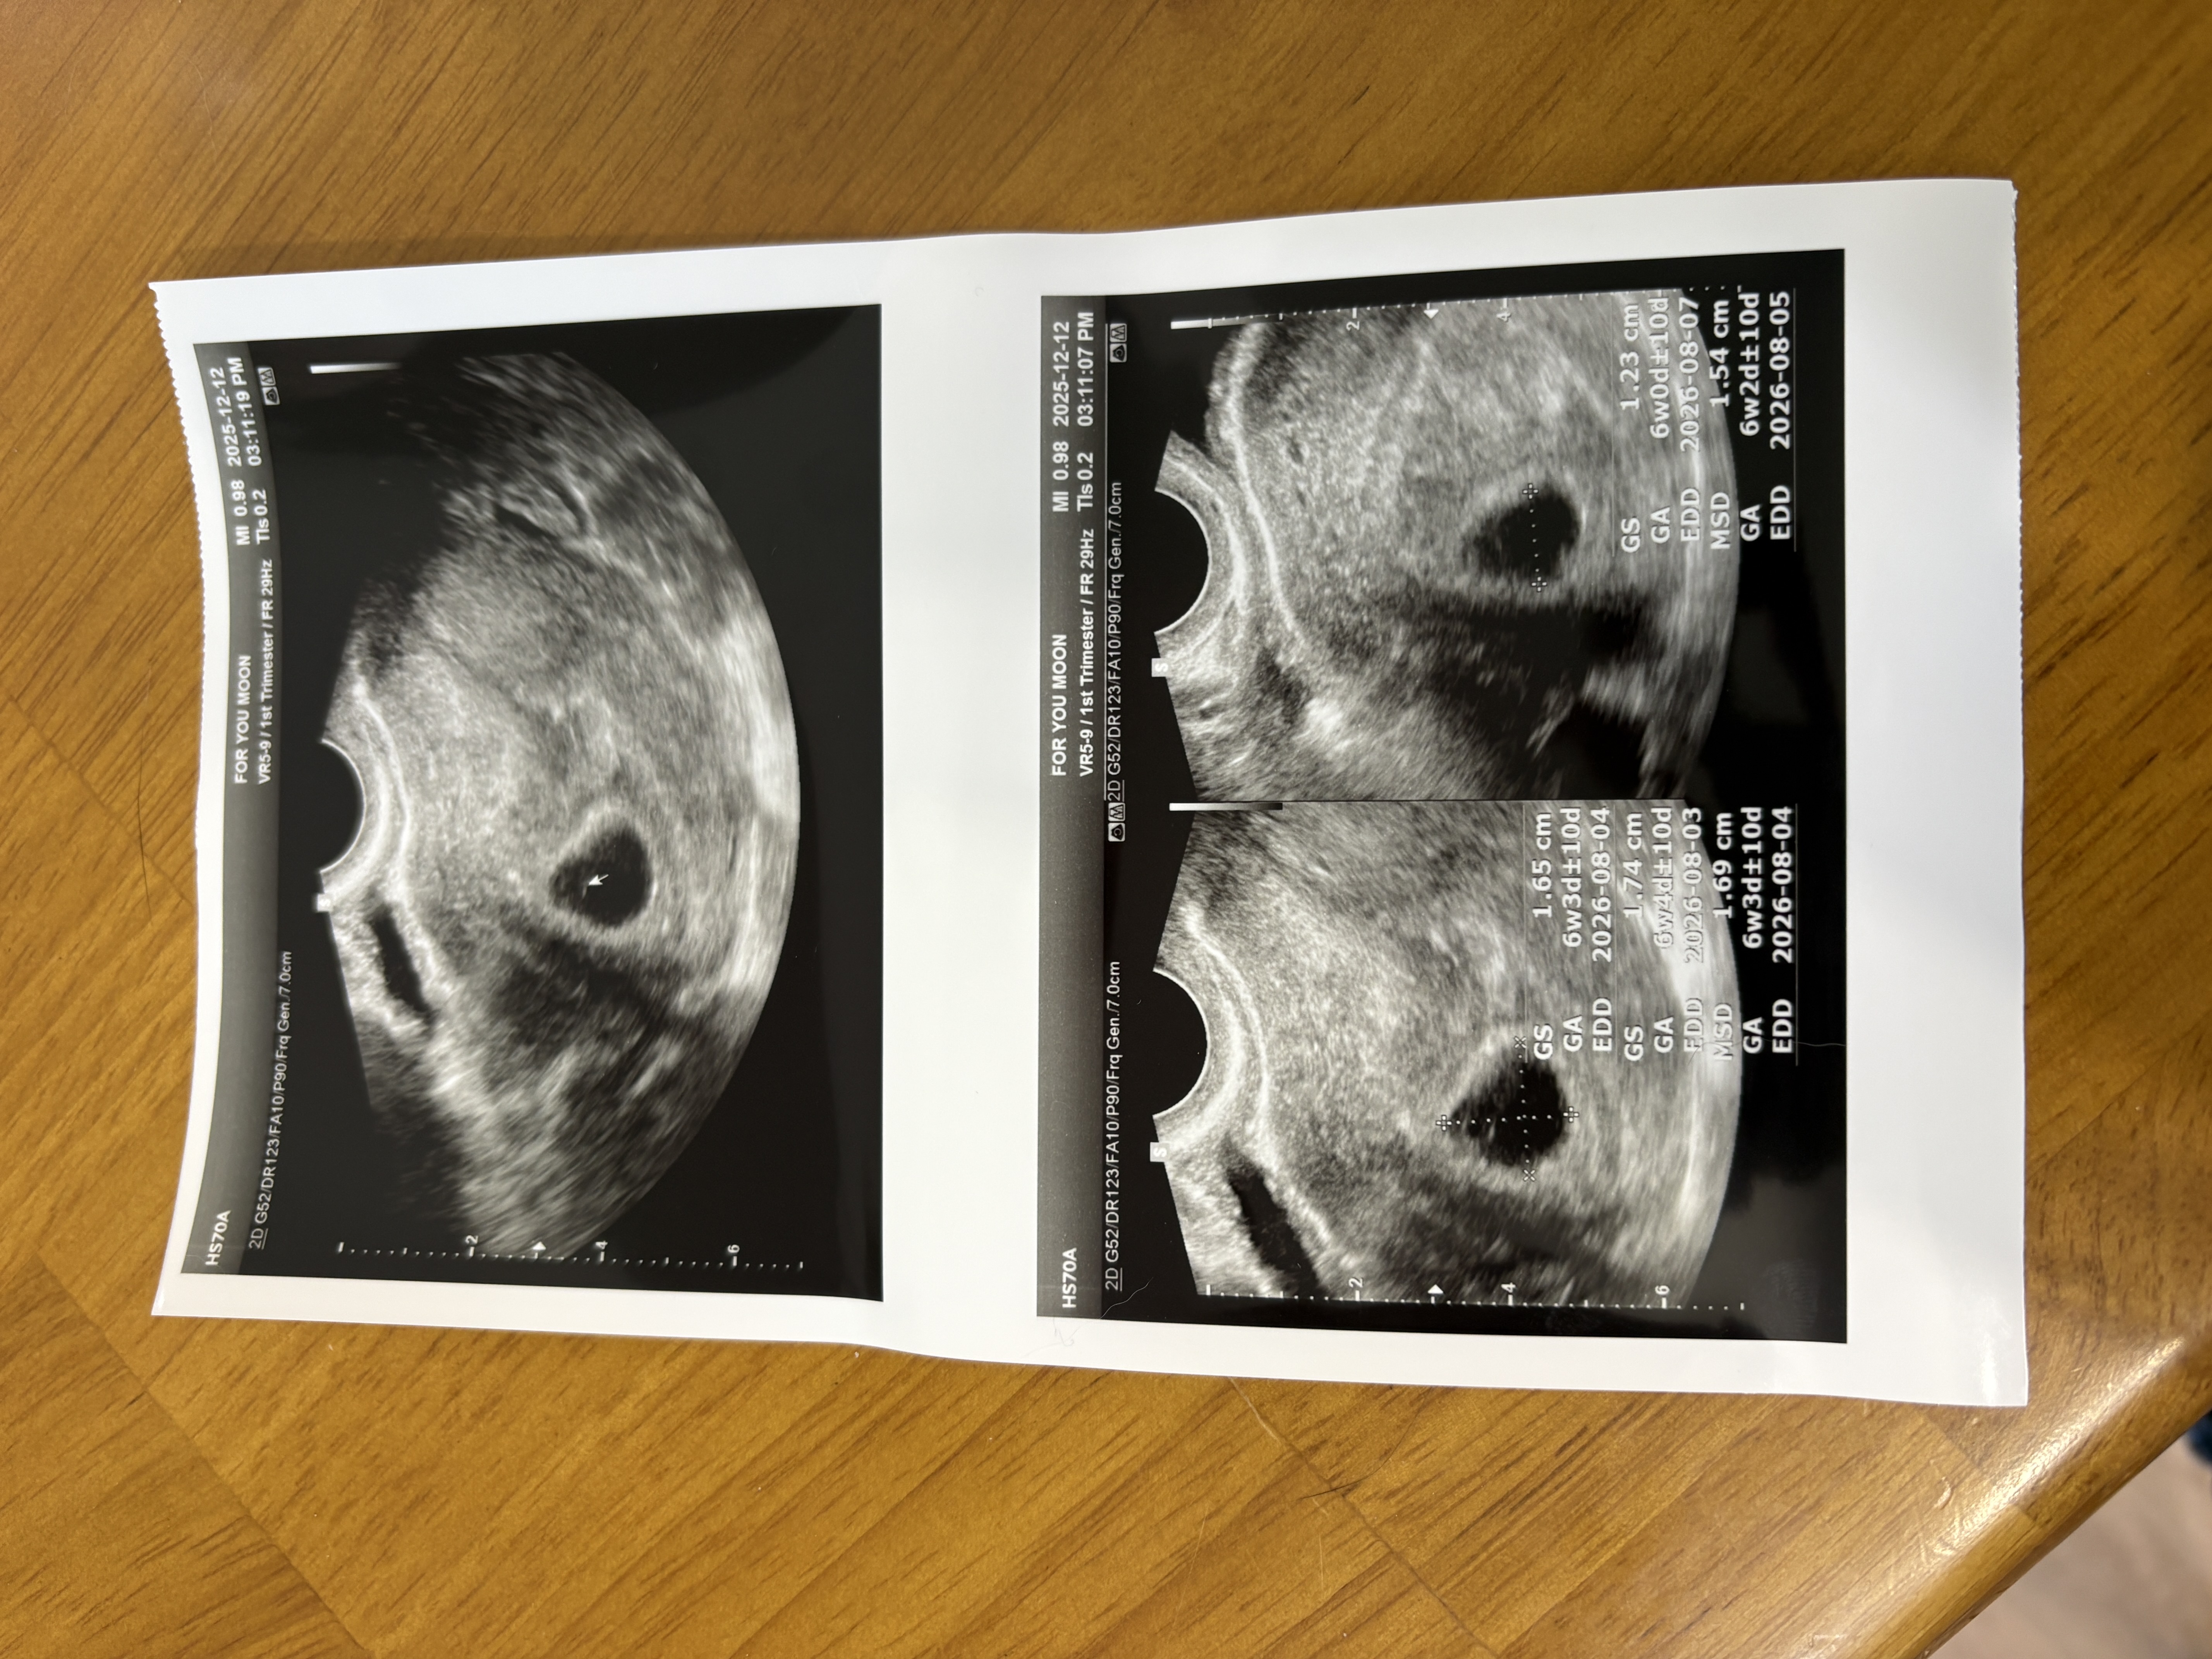

현재 애기집 난황 다 보이는데 아직 애기가 안보인데요 특별히 문제는 없고 온갖 검사 다 정상인데 아직 안보일 수도 있다고 하지만 조바심나네요 평소 생리주기가 길고 불규칙해서 수정이 정확히 언제됐는지 그래서 아직 정확한 주수는 알 수 없다고 듣긴 했는데 6주 정도인데 아직 애기가 안보인다니 혹시 저 같은 분들도 계신가요? 심장소리 빨리 듣고싶어요 ㅠㅠ